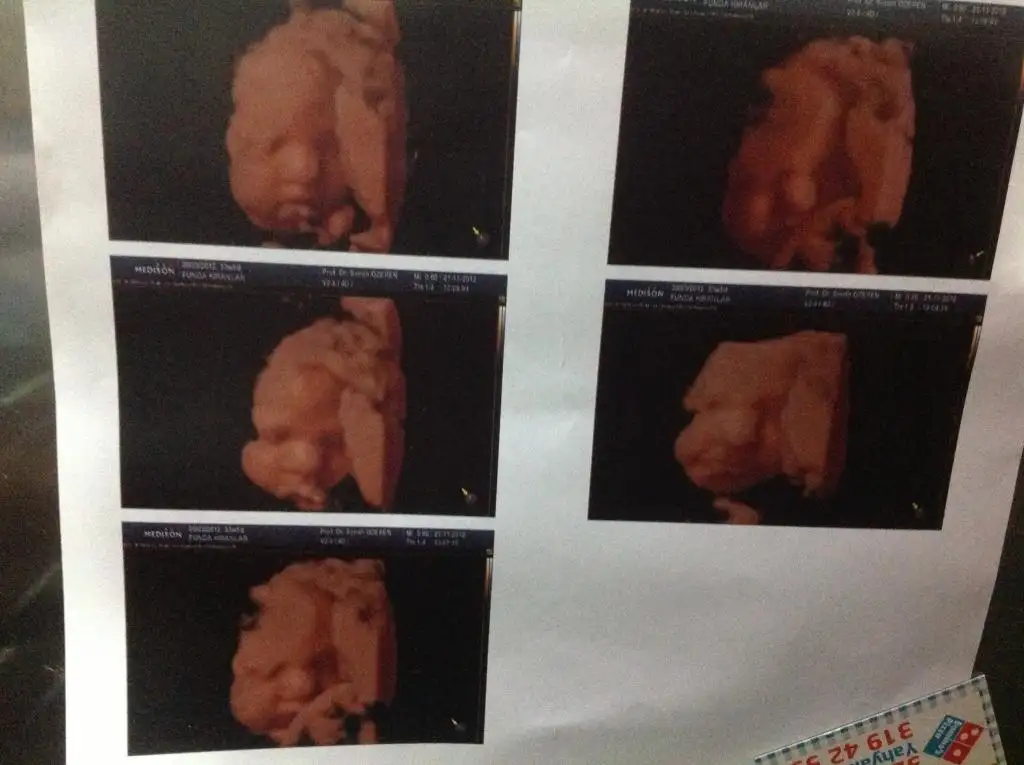

benim bugün kontrolüm vardı. Çok şükür iyi oğluşko. 49 cm boyu, 3300 kilosu olmuş. NST'de normal çıktı herşey. Herkeste olduğu gibi ağrılarım ama hepsi normalmiş. 7 aralık kısmetse saat 9.00 da sezeryen için randevumuz var :)